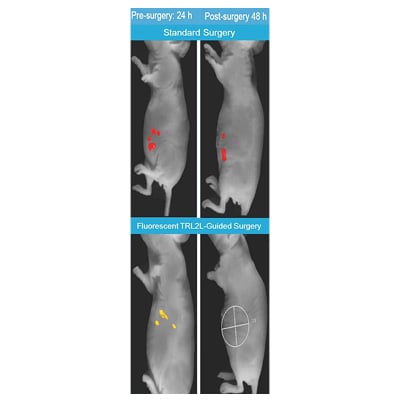

The Toll-like receptor 2 ligand, TLR2L, is a novel, fully synthetic lipopeptide developed and optimized using the MALP-2 lipopeptide as a starting scaffold platform. This probe has a simplified synthetic route compared to the scaffold. TLR2L binds TLR2 with high affinity (24nM Ki) as determined by competitive binding to living cells. It was also designed with a linker and attachment point for greater ease in conjugating imaging contrast molecules, and it retains high affinity following conjugation to either IRDye800CW® (11nM Ki) or Eu-DPTA (34nM Kd). TLR2L-800 displayed significant affinity and selectivity for TLR2-expressing tumor xenografts in nude mice (p<0.001). Preliminary PK/PD studies show that at all dosages, the probe had cleared from normal tissues by ~3hr, from the kidneys by 24hr, but was retained in the positive tumor for up to 96hrs. A pre-clinical efficacy study showed that all the mice whose tumors were removed using TLR2L-800 fluorescence-guidance (n=5) had no remaining cancer cells in the pancreas, when compared to a control group of mice whose tumors were removed using standard non-guided surgeries (n=3) where all of the mice had remaining cancer cells in the pancreas (p=0.018).